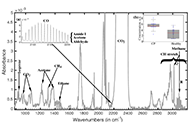

DOI: https://doi.org/10.37349/emed.2025.1001309 Breath analysis using FTIR spectroscopyOpen AccessReviewBreath analysis is a relatively new topic of study that has a lot of potential for both therapeutic and scientific applications. The volatile organic compounds (VOCs) found in breath are created int [...] Read more.Andrei A. Bunaciu, Hassan Y. Aboul-EneinPublished: April 17, 2025 Explor Med. 2025;6:1001308

Breath analysis using FTIR spectroscopyOpen AccessReviewBreath analysis is a relatively new topic of study that has a lot of potential for both therapeutic and scientific applications. The volatile organic compounds (VOCs) found in breath are created int [...] Read more.Andrei A. Bunaciu, Hassan Y. Aboul-EneinPublished: April 17, 2025 Explor Med. 2025;6:1001308

DOI: https://doi.org/10.37349/emed.2025.1001308 Joint mobilization strategies for chronic ankle instability: comparing active and passive approaches in a randomized controlled trialOpen AccessOriginal ArticleAim: This study aimed to evaluate the differential effects of active joint mobilization (AJM) versus traditional passive joint mobilization (PJM) in individuals with chronic ankle instability. We [...] Read more.Hyunjoong Kim ... Mingyun KoPublished: April 17, 2025 Explor Med. 2025;6:1001307